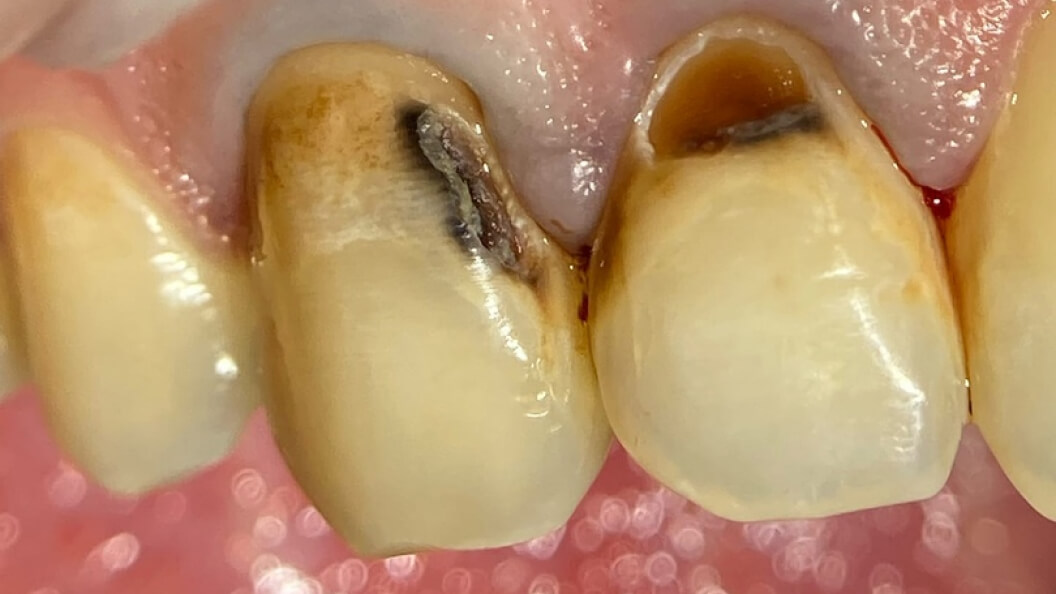

Пациентка обратилась в «Стоматологию Комфорта» с жалобами на эстетический дефект передних зубов. Врач Галухина Карина Николаевна во время осмотра выявила кариозные полости на 1.2. и 1.3 зубах. Было решено провести лечение с помощью пломбировочного материала Vitremer A3. Врач также рекомендовала рациональную гигиену полости рта после лечения.

Пломбировочный материал Vitremer имеет 3 механизма отверждения, что благотворно влияет на краевое прилегание к зубу, а также качественную адгезию. При этом все области полноценно заполняются при нанесении 1 порции материала. Масса является интактной: пломба отличается долговечностью, риск выпадения сведён к минимуму. Vitremer препятствует развитию кариозных процессов.